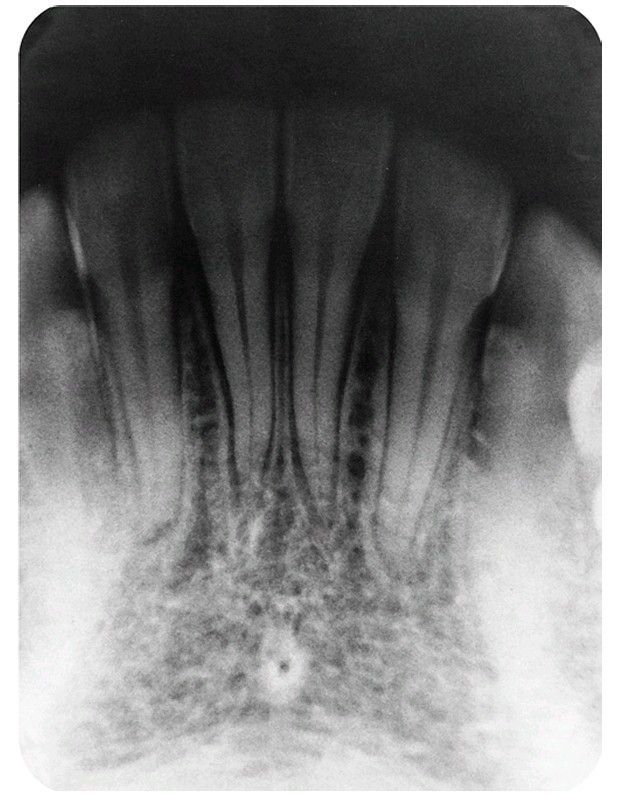

Radiograph showing widened periodontal ligament spaces around several teeth that are displaced coronally.